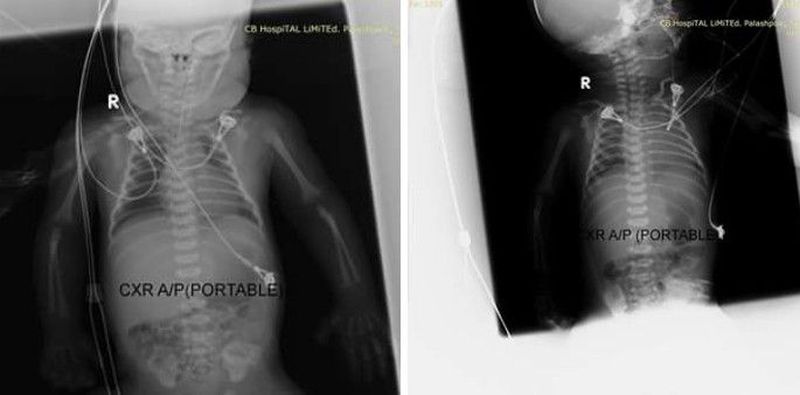

Dx?NEC?

Premature

Pneumatosis

Necrotizing Enterocolitis

Pneumatosis Intestinalis in Necrotizing Enterocolitis